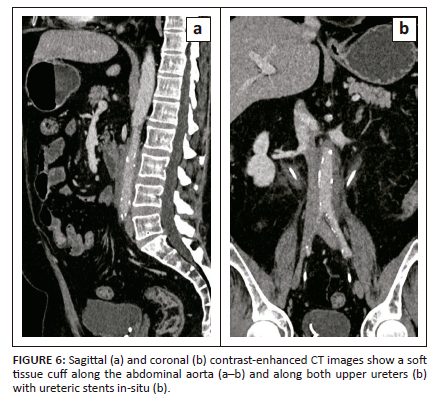

A 58-year-old male who had undergone bilateral DJ stenting for non-calculous ureteric obstruction was referred for CECT abdomen to evaluate for the cause of the obstruction. Initially, the patient had presented with bilateral renal colic with bilateral hydronephrosis on ultrasonography and no evidence of renal or ureteric calculi. The patient did not undergo CECT at that time due to deranged renal function. The patient subsequently underwent DJ stenting, after which the CECT was performed as the renal function tests normalised. The CT images revealed a circumferential cuff of non-enhancing soft tissue surrounding the abdominal aorta and both upper ureters with periureteric fat stranding causing luminal narrowing of the ureters and aorta (Figure 6a and 6b). A presumptive diagnosis of retroperitoneal fibrosis was made and the patient was evaluated for autoimmune pathology which revealed markedly elevated IgG4 levels (275 mg/dL). The patient started steroid therapy and is under follow-up.